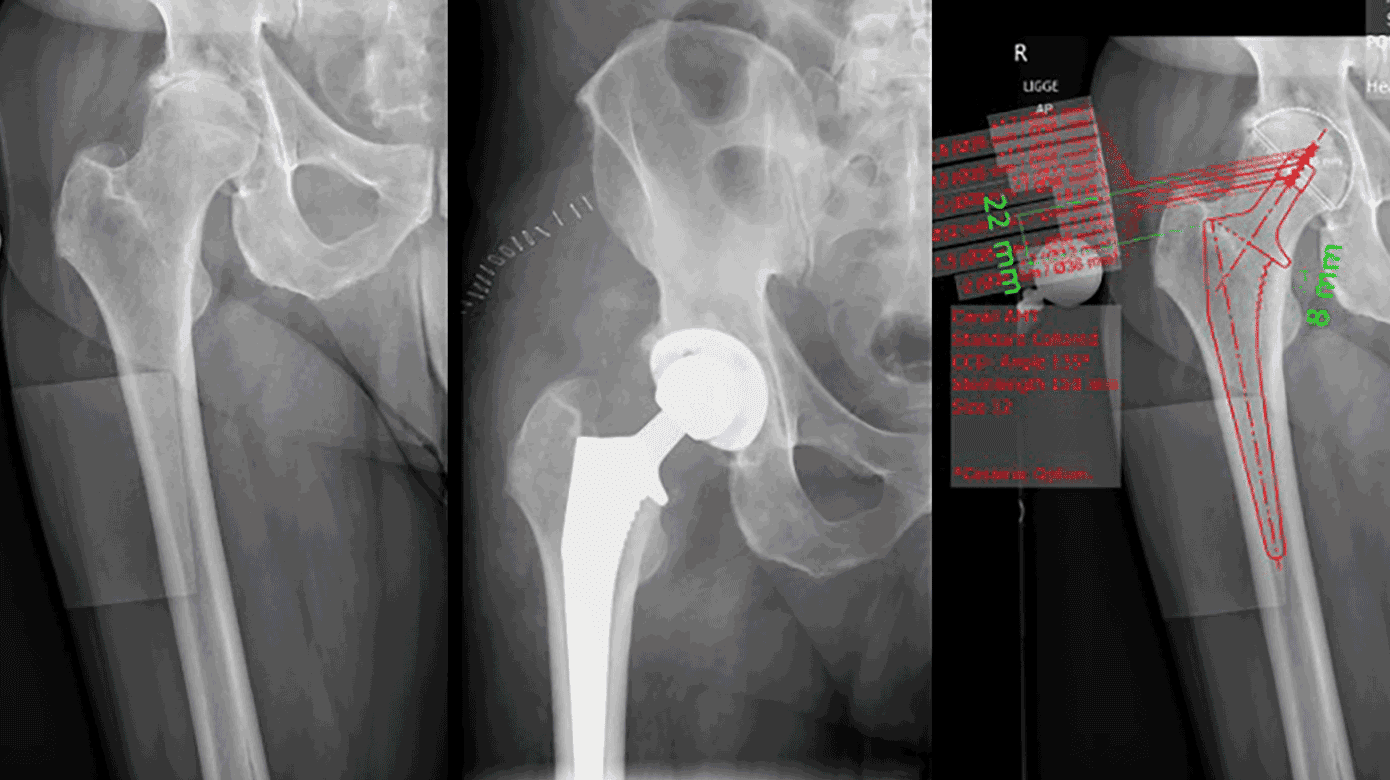

Templating af hofterøntgenbilleder er en afgørende procedure, når man forbereder sig på en hofteoperation, særligt i forbindelse med hofteledsalloplastik [1]. Ved at bruge røntgenbilleder til at planlægge den præcise størrelse og placering af de kunstige leddele får ortopædkirurgen et klart overblik, hvilket både øger nøjagtigheden under operationen og mindsker risikoen for komplikationer (Figur 1).